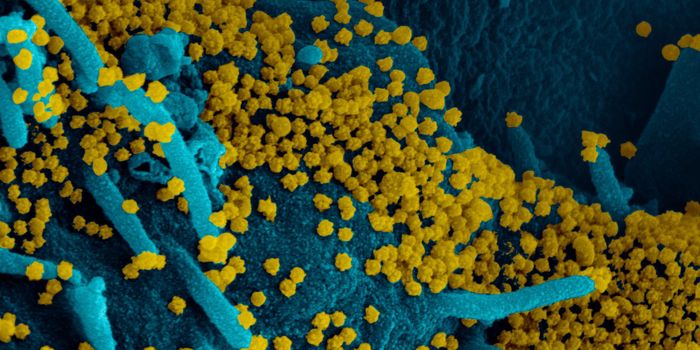

MAY 03, 2020Genetics & GenomicsThe origin of SARS-CoV-2, the pandemic virus that causes COVID-19, has become politicized as leaders seek to place blame ...

JUL 06, 2020MicrobiologyThe pandemic coronavirus has caused a wide range of different symptoms, and as time goes on, we may find that it can hav ...

JUL 05, 2020Cell & Molecular BiologyThe pandemic virus SARS-CoV-2 enters the body through the respiratory system to cause the illness COVID-19. But we know ...

JUN 29, 2020MicrobiologyVaccines that contain live attenuated viruses may be giving people some protection from serious cases of COVID-19 that i ...

FEB 22, 2021MicrobiologyReporting in Science, researchers have created an antiviral nasal spray that could help us get the COVID-19 pandemic und ...

SEP 01, 2021MicrobiologyIt's been generally assumed that people who get infected with SARS-COV-2 will develop antibodies to the virus, which cau ...

MAR 18, 2020MicrobiologySARS-CoV-2 is a coronavirus that causes an illness called COVID-19. There are now well over 210,000 confirmed cases worl ...